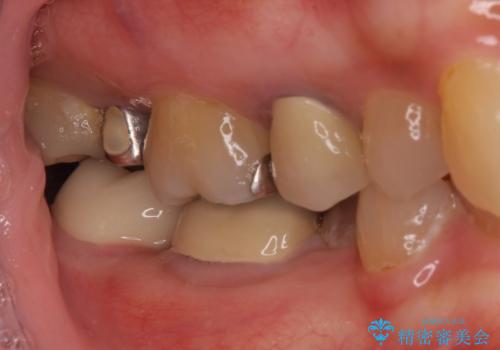

インプラント埋入にあたり、歯槽骨での炎症が広範囲であったことから、事前に骨造成を行いました。

歯槽骨の高さや幅を回復することができ、望ましい位置にインプラントを埋入することができました。